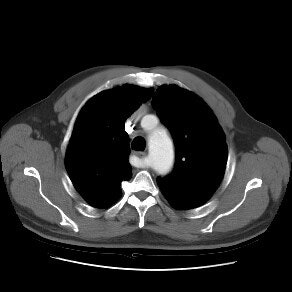

Aberrant right subclavian artery with a left aortic arch

The CT image below demonstrates an aberrant right subclavian artery arising as the last branch from the aortic arch. In this case the vessel is not arising from a diverticulum. The vessel travels to the right posterior to the esophagus.